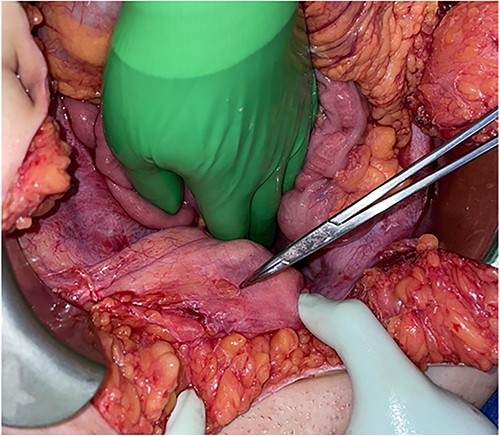

A blunt marking pen was identified in the right upper quadrant, lying on top of the omentum (Fig. 2). Inspection of the bladder revealed a 1-cm round defect in the dome of the bladder (Fig. 3). This was oversewn in two layers, with a subsequent negative leak test. The rest of the abdomen was inspected with no injuries identified to the colon, small bowel, uterus or ovaries. Lastly, the abdomen was washed out and closed. A Foley catheter was left in place and a drain was left by the area of bladder repair.

Round defect in the dome of the bladder (pointed with the tip of Tonsil Forceps).